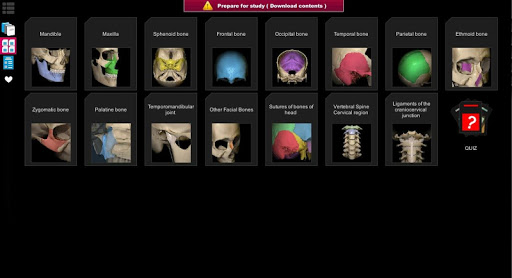

A true and totally 3D app for studying human anatomy, built on an advanced interactive 3D touch interface.

★ 3D location quizzes to test your knowledge

★ Bones

★ Ligaments

★ Joints